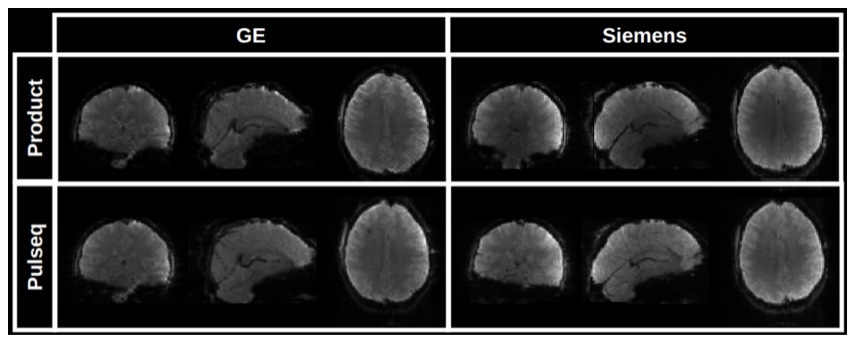

Image reconstruction

To reconstruct images from the acquired raw (k-space) SMS-EPI data, the user is free to choose from several available image reconstruction pipelines. The HarmonizedMRI development team has implemented both 3D SENSE27 and slice GRAPPA28 SMS-EPI reconstructions in MATLAB that are part of the QA protocol described below. Other community-developed implementations are also available.29–33 Figure 5(b) shows the results of reconstructing Pulseq SMS-EPI data using 3D SENSE27 implemented in BART.32 Figure 6 demonstrates that our Pulseq protocol achieves similar image contrast and overall image quality as the matched product protocols.

In our current workflow, image reconstruction is done with slice GRAPPA due to its fast computation speed and robust image quality, and zero-filling partial Fourier (PF) reconstruction. Other choices are possible, such as multi-coil reconstructions with spatial regularization, and homodyne PF reconstruction. The extent to which these image reconstruction and post-processing choices impact fMRI reproducibility is an open research question.